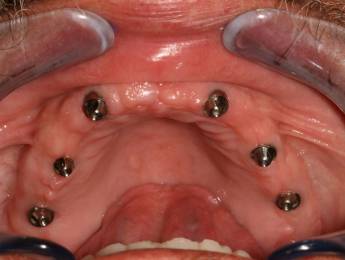

3. eset

4 implantátumra rögzített stéggel stabilizált "Overdenture" megoldás. Költséghatékony módszer fogsorok rögzítésére. Nagyfokú stabilitás érhető el redukált felületeken. Ebben az esetben jól látható, hogy a szájpadlást nem fedi be a kivehető fogsor, az ízlelés is megmarad, mégis javul a rágási képesség és a fogsorok mozgásmentesen rögzülnek.